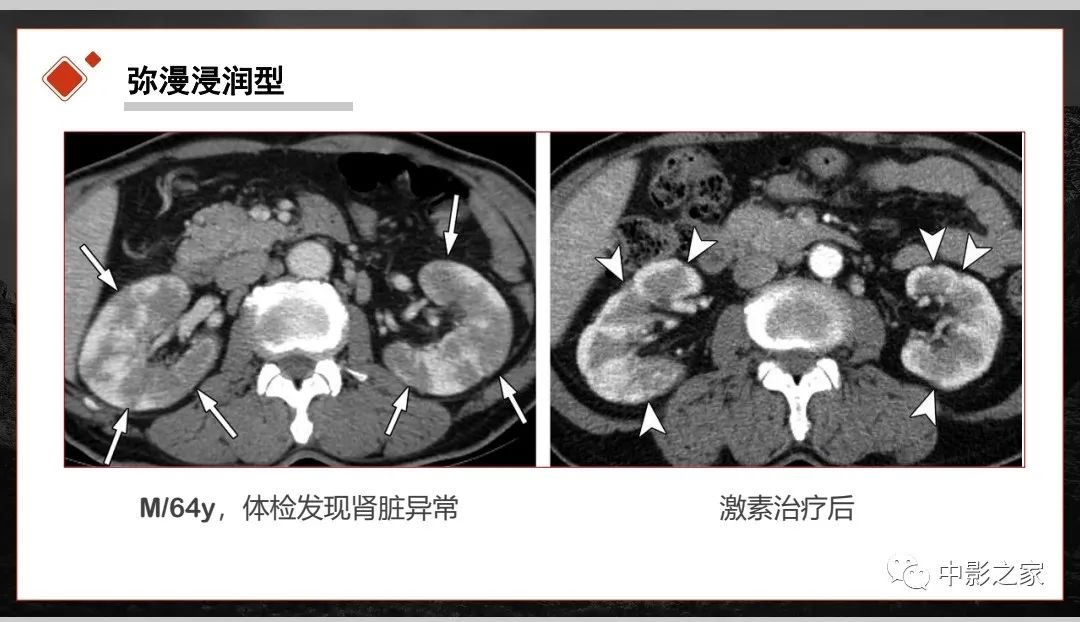

肾脏IgG4-RD临床、病理及影像特征